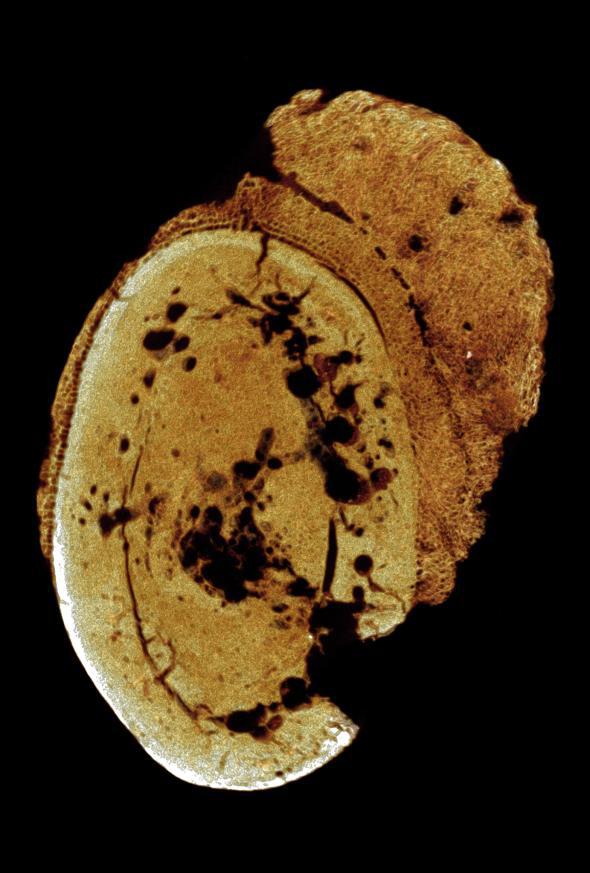

Imagine de tomografie computerizată a osului afectat de cancer (Foto:nationalgeographic.com/Patrick Randolph-Quinney/UCLAN)

Ambele fragmente osoase au fost identificate în peşteri din zona aşa-numitului ,,Leagăn al Omenirii”, un areal din Africa de Sud în care au fost descoperite numeroase dovezi ale prezenţei primelor specii de hominizi. Fosilele scoase recent la lumină au fost analizate cu ajutorul unor tehnici de imagistică 3D, ce au pus în evidenţă faptul că strămoşii noştri suferisă încă de acum 1,7 milioane de ani din cauza osteosarcomului.

Osul afectat de cancer, văzut dintr-un alt unghi (Foto:nationalgeographic.com/Patrick Randolph-Quinney/UCLAN)